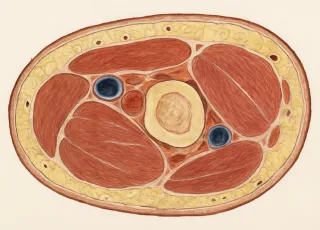

МРТ мягких тканей на Каширском шоссе в Москве применяется при подозрении на наличие каких-либо патологий. Оно используется для установления заболеваний кожи, подкожной клетчатки, сухожилий, суставных капсул, нервных и железистых тканей. Таким образом магнитно-резонансная томография выявляет изменения в мягких тканях человеческого организма, где отсутствует части костного скелета. Это исследование также активно применяется среди спортивных врачей. Они по МРТ отслеживают как протекает процесс восстановления у спортсменов после травм.

МРТ мягких тканей проводится при следующих симптомах и проблемах:

- Боли в мышцах, связках, сухожилиях.

- Подозрение на разрыв или повреждение мягких тканей.

- Диагностика спортивных травм (повреждения плеча, колена, голеностопа).

- Выявление опухолей и кист мягких тканей.